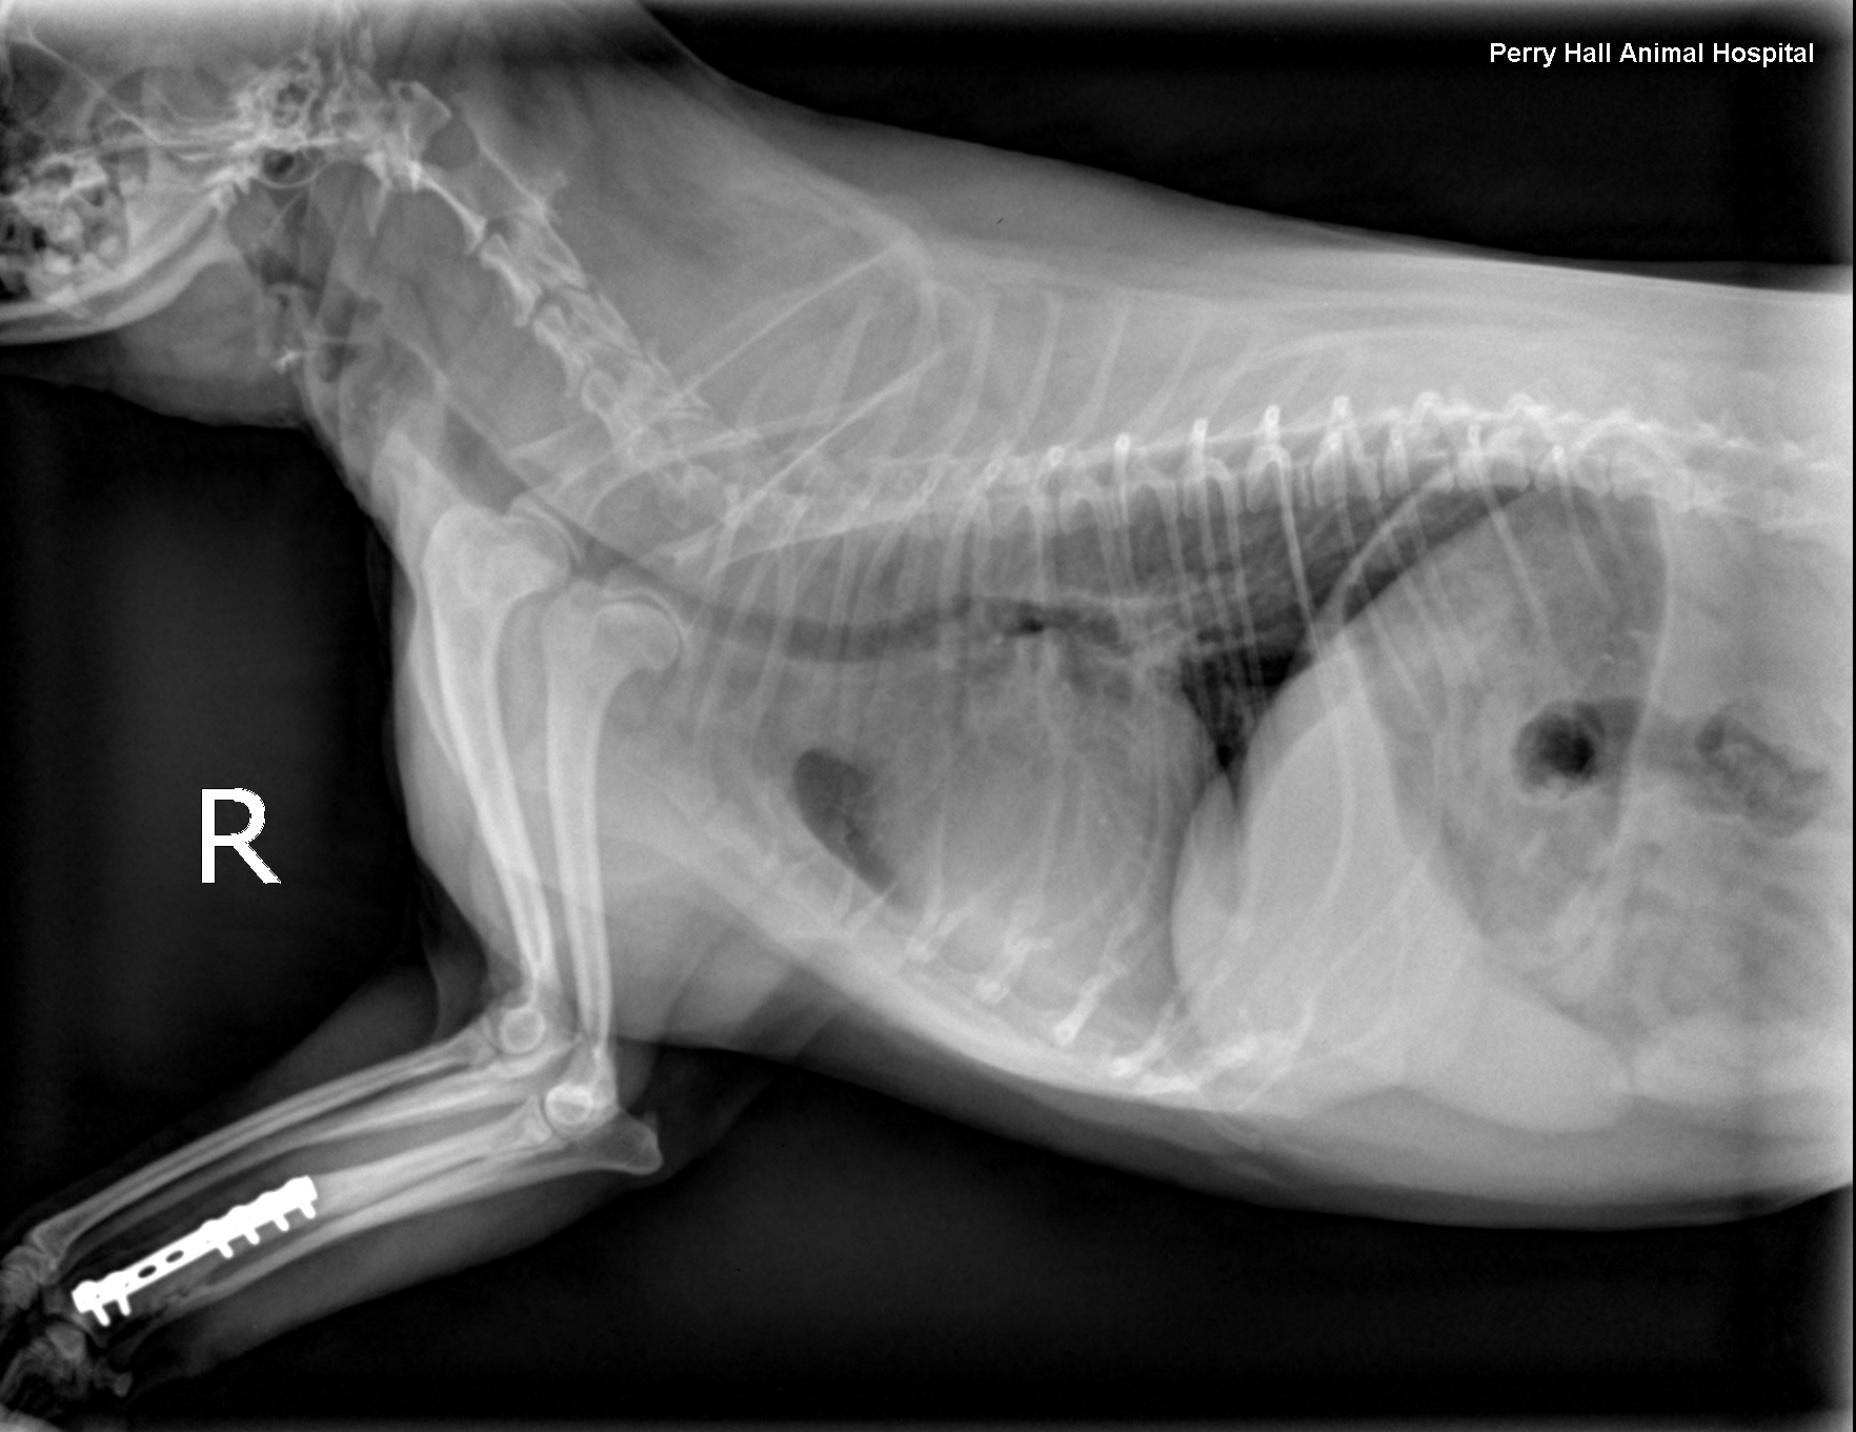

Rads- Left lateral, right lateral and VD views of the thorax and neck. One of the lateral views was obtained in fair inspiration (degree of inspiration reduced as a function of the disease), one was an expiratory view. There was mild to moderate rotation of the trunk in the lateral views. There was superimposition of the front limbs with the cranial thorax. The hands of the holding person were in the primary beam during exposure which is strictly prohibited.

Intrathoracic structures: The chest volume was small. There was an intrathoracic tracheal collapse and collapse of the main stem bronchi on the expiratory view. The height of the trachea was reduced by more than 50 % as compared with the inspiratory view. The tracheal lumen was reduced to a height of 2mm level with the thoracic inlet when collapsed. The cardiac silhouette was normal for size and shape. The major vessels were within normal limits. The pulmonary vessels and caudal vena cava were within normal limits. No mediastinal widening was noted.

The lungs showed diffuse increase in opacity caudodorsally on the expiratory view

The radiographic findings are compatible with dynamic tracheal and bronchial collapse likely due to bronchomalacia.